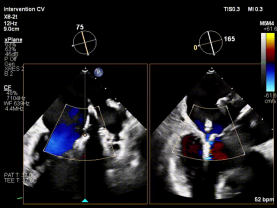

【图片7-9:术中定位、夹持过程及术后效果图】

术后评估显示,患者二尖瓣反流由极重度明显降低至中度以下,血流动力学改善,手术取得良好效果。